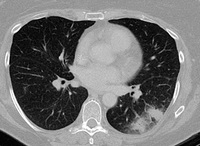

Signo de "creciente aéreo" en la aspergilosis pulmonar tardía

De la colección del Dr. P. Chandrasekar; utilizada con autorización